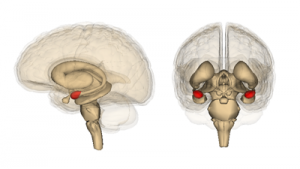

Мозжечковая миндалина – это специфическая часть мозга, визуально напоминающая по форме обычную миндалину. Ее дислокация находится в глубине височной доли головного мозга, на латыни “доля” носит название Lobus temporalis. Каждое полушарие головного мозга обладает своей миндалиной. Значение этих миндалин сложно переоценить, ведь они участвуют в формировании эмоций, являются составным элементом лимбической структуры.

Миндалина (миндалевидная железа, амигдала, мозжечковая мигдалина, лат.ncorpus amygdaloideum) является набором нейронов миндалевидной формы,nрасположенных глубоко в медиальной височной доли мозга.

Миндалина (миндалевидная железа, амигдала, мозжечковая мигдалина, лат. corpus amygdaloideum) является набором нейронов миндалевидной формы, расположенных глубоко в медиальной височной доли мозга.